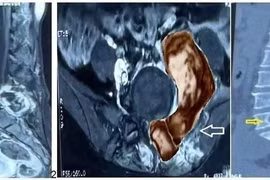

Lần đầu tiên tại Việt Nam, thay vì chỉ phẫu thuật giảm nhẹ để phục hồi và bảo tồn chức năng thần kinh, các bác sĩ Bệnh viện Đại học Y Hà Nội đã tiến hành lấy bỏ toàn bộ đốt sống, bao gồm trọn vẹn thân đốt sống chứa u và cung sau để điều trị triệt căn cho người bệnh.

(khoahocdoisong.vn) - Cột sống là xương trục chính, là giá đỡ cho các cơ quan quan trọng. Các khối u di căn thường xảy ra ở đây. Bệnh sử và kết quả khám ở bệnh nhân u cột sống không liên quan trực tiếp đến tình trạng bệnh hiện tại nên bệnh nhân cần nắm rõ biểu hiện của u cột sống để thông báo cho bác sĩ.